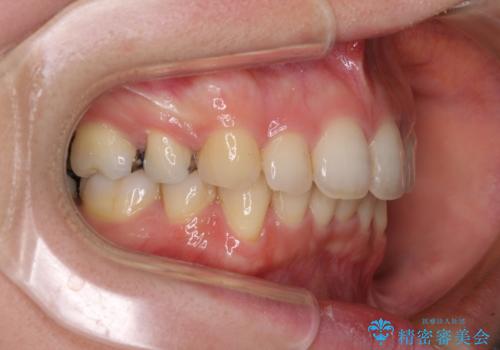

- 上下の出っ歯を気にして来院された患者様です。

口元を積極的に引っ込めるために、上下左右の第一小臼歯を4本抜歯することとしました。

元々ディープバイトのため、スペースを閉じている期間に上下前歯が接触してしまい、治療期間が想定よりも伸びてしまいました。